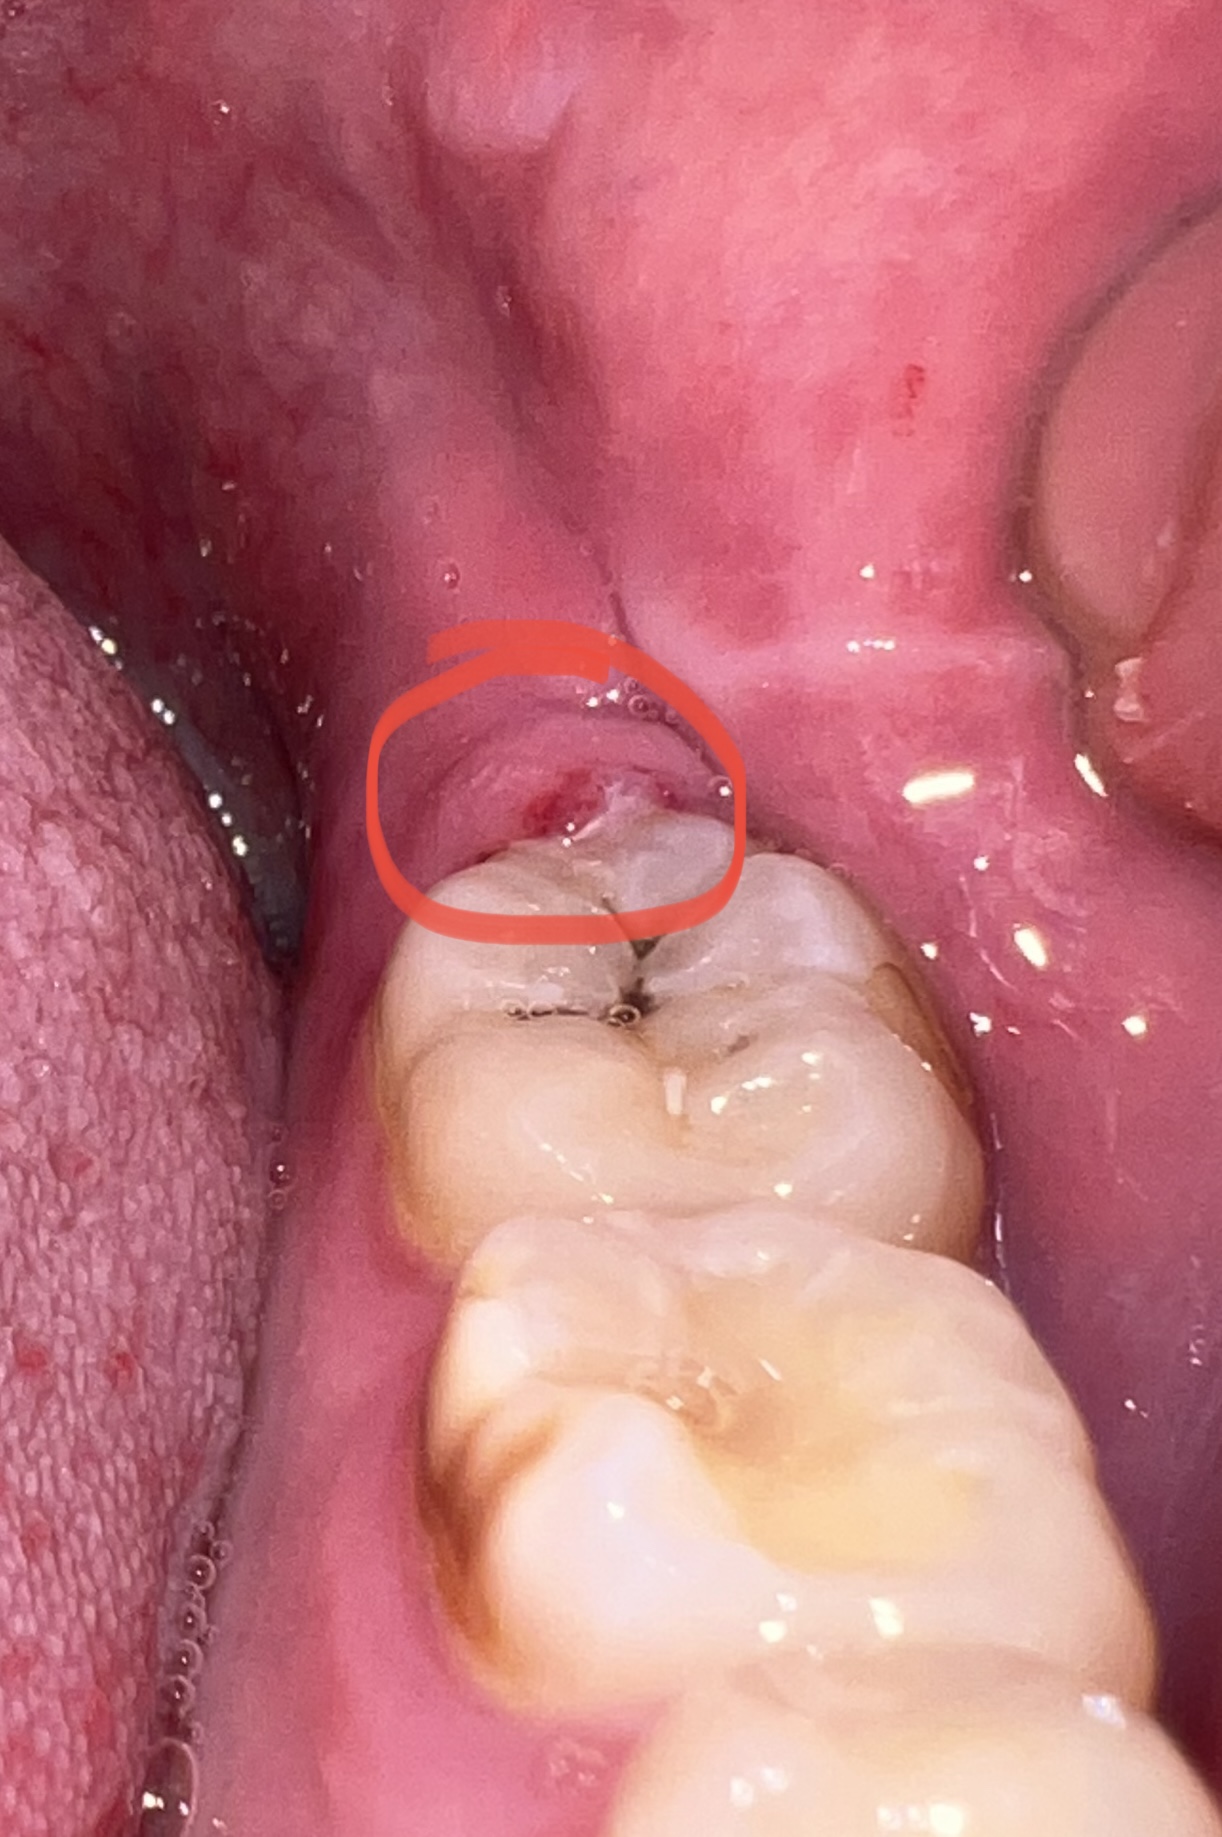

Sinds een aantal dagen heb ik een klein wondje op mijn tandvlees achter mijn laatste kies (linksonder vanuit mijzelf gezien).

Het wondje wad eerst iets witter en nu alleen maar rood (op de eerste foto is een stukje wit te zien).

Sinds een aantal dagen heb ik een klein wondje op mijn tandvlees achter mijn laatste kies (linksonder vanuit mijzelf gezien).

Het wondje wad eerst iets witter en nu alleen maar rood (op de eerste foto is een stukje wit te zien).

Ik heb vanmiddag mijn tandarts gebeld en het uitgelegd. Mij werd verteld dat het een aft of ontstoken tandvlees was en dat ik een mondgel met lidocaïne zou kunnen gebruiken. Deze heb ik nu in huis gehaald en smeer ik er voor het slapen gaan op.

Gezien de foto lijkt het mij…

".Een afte (stomatitis…